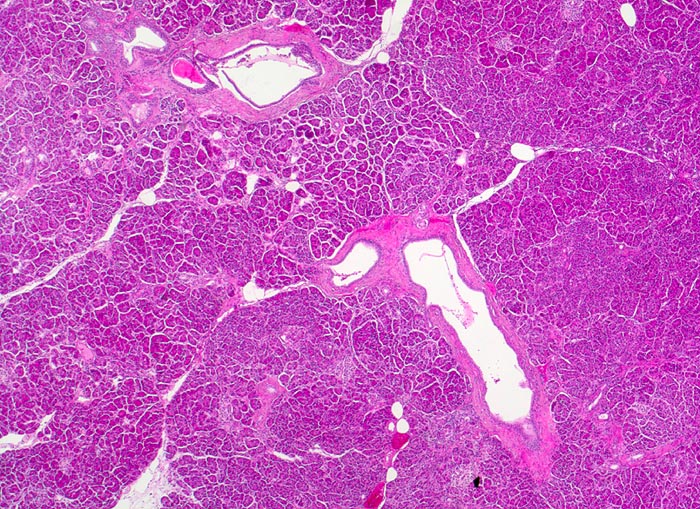

Fast alle exokrinen Drüsen sind betroffen. Pankreasgänge, intestinale Drüsen, intrahepatische Gallengänge und die Glandula submandibularis sind obstruiert durch visköses oder solides eosinophiles Material. Tracheobronchiale und Brunner’sche Drüsen bilden vermehrten Schleim. Schweissdrüsen, kleine Speicheldrüsen und Glandula Parotis sind histologisch normal, sezernieren aber vermehrt Natrium und Chlorid. Veränderungen in der Lunge ( 3689) entwickeln sich als Folge von Luftwegsobstruktion und Infekten (initial vor allem mit Staphylococcus aureus, später meist Pseudomonas aeruginosa).